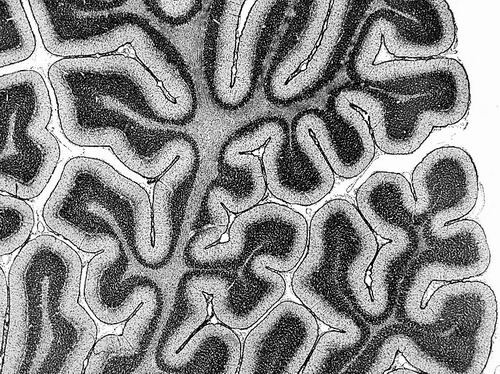

随着人的成长,大脑中协同工作的区域会发生变化。图片来源:Microscape

科学家绘制出首份关于大脑活动关键模式的图谱,并确定了这些模式在人类整个生命周期中的变化规律。3月25日,相关研究成果发表于《自然》。

这份图谱基于近3600人的脑部扫描数据,年龄跨度从婴儿到百岁老人。它映射了一种名为“功能连接”的特性,描述了不同脑区之间的协调水平。数据表明,在年轻人中,这种连接的特定模式与认知表现有关。

大脑是一个“吵闹”的地方。有时两个相距甚远的大脑区域会同时活跃,表明它们在协同工作以支持相同的功能。这些区域被认为是“功能性连接的”,尽管它们在大脑中未必相邻。

论文作者、美国北卡罗来纳大学教堂山分校的Patrick Taylor解释说,为理解这种功能性连接是如何组织的,研究人员会根据它们与大脑其他部分的连接模式,将大脑区域沿着一个比例或轴线绘制出来。这里有3个主要的功能轴。例如,感官-联想轴使研究人员能够描述沿该轴分布的脑区——从主要专注于处理感官信息的区域到参与复杂过程的区域。轴上各点的脑区具有相似的连接模式。

感官-联想轴的一端是与感官处理密切相关且与其他具有相同功能的区域相连的脑区。而轴的另一端则是支持更高层次信息处理并与众多其他区域相连的脑区。位于轴中间的是充当过渡地带的脑区,将感官处理与更抽象的思维联系起来。这意味着这些区域在功能上既与感官网络相连,又与参与复杂思维的区域相接。